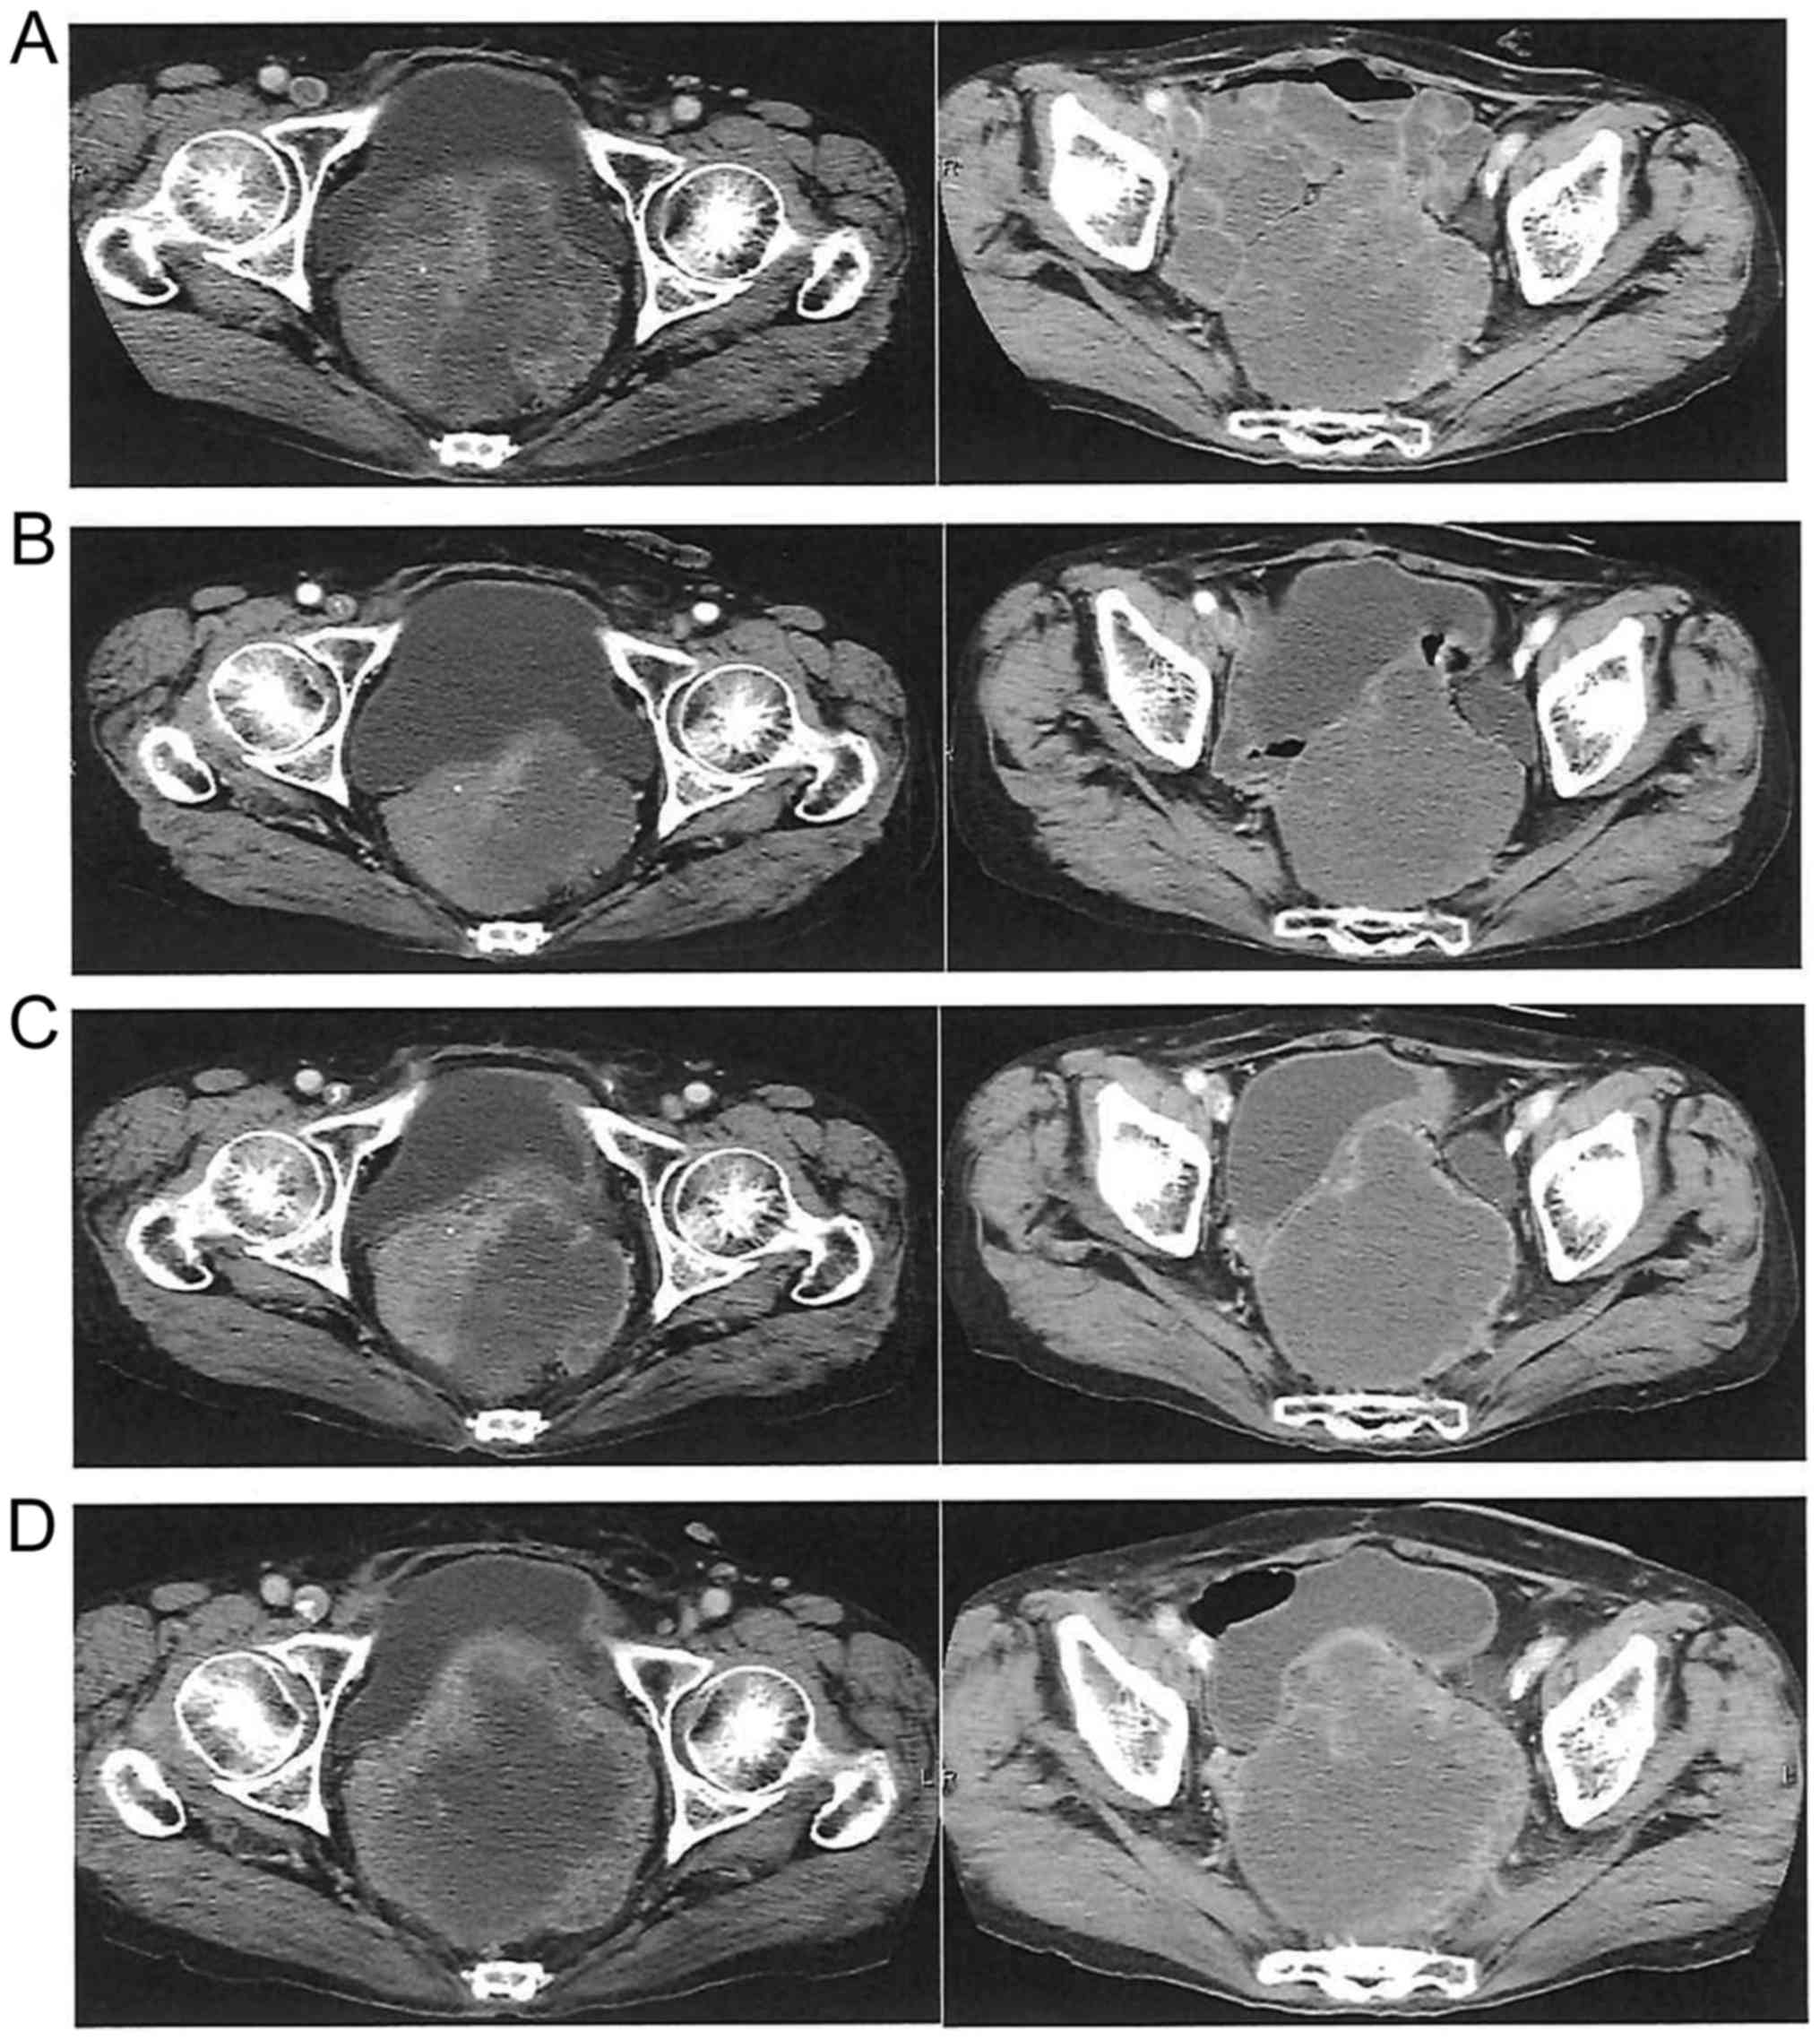

Figure 3.

Efficacy of regorafenib at 120 mg/day in a female patient please confirm who received 9 cycles of treatment and achieved partial response. (A) Pretreatment computed tomography scan. (B) Shrinkage of local recurrence and decrease of internal density after 3 cycles. (C) Change in size and internal density after 6 cycles. (D) Increased size and internal density after 9 cycles, indicating progressive disease.

None of the patients achieved complete response; however, 1 patient achieved partial response (PR) and 9 had stable disease (SD). The objective response rate was 5.6% and the disease control rate (DCR) was 55.6% (Table III). Two patients who were treated with the dose of 120 mg were able to receive Reg for >6 cycles: One was a 66-year-old woman with local recurrence who received five prior chemotherapies with Bmab, Cmab, panitumumab, L-OHP, CPT-11 and FUs. The patient was started on Reg as sixth-line chemotherapy, and after three courses of Reg, the local recurrence exhibited a PR and the radiological tumor density decreased, with cystic changes of the lesion. The patient was eventually treated with Reg until the ninth cycle (6.5 months) (Fig. 3). The other patient was a 64-year-old man with multiple lung and liver metastases who received five prior chemotherapies; he was also started on Reg as sixth- line chemotherapy and, after two courses of Reg, formation of a cavity in a lung metastasis with intralesional cystic change of the liver metastases were observed. The patient received treatment with Reg until the sixth cycle (5 months) (Fig. 4). The median OS was 204 days (Fig. 2A) and the PFS was 77 days (Fig. 2B) in all the patients.